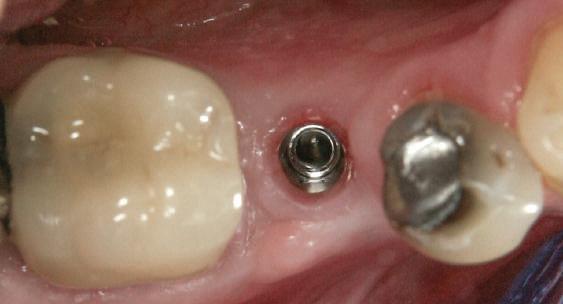

Alt caz (1) Figurile

4. După osteointegrarea implantului 2.4., s-a observat recesia în etapa de amprentare a implantului 2.5.; s-a decis reprepararea marginilor bontului individualizat CAD/CAM 2.4. Înainte de preparare s-a aplicat şnur de retracţie pentru a evita lezarea ţesutului şi a îmbunătăţi vizibilitatea dintelui 2.3. şi a marginii bontului implantar individualizat. Aşa cum era de aşteptat, recesia a fost mai mare de-a lungul versantului distal al bontului 2.4. adiacent locului de extracţie vindecat/cu implantul mai nou.

5. Bontul individualizat aplicat (2.5.) cu bontul repreparat anterior (2.4.). Nu a survenit recesie nouă de o perioadă de peste 3 ani.